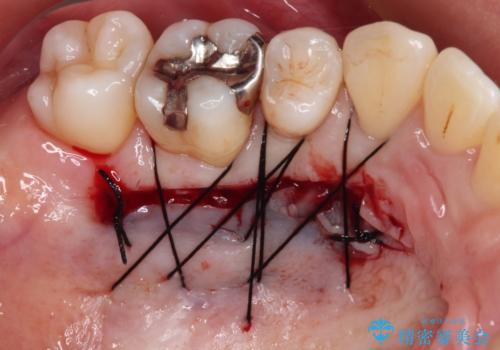

歯肉退縮に対して、上顎からの結合組織移植術(CTG)により、歯根の被覆を行うとともに、歯肉の厚みを増すことで将来の退縮リスクを抑制することとしました。

被覆量が不十分の場合には、追加で手術を行うことで患者様の了解を得ました。